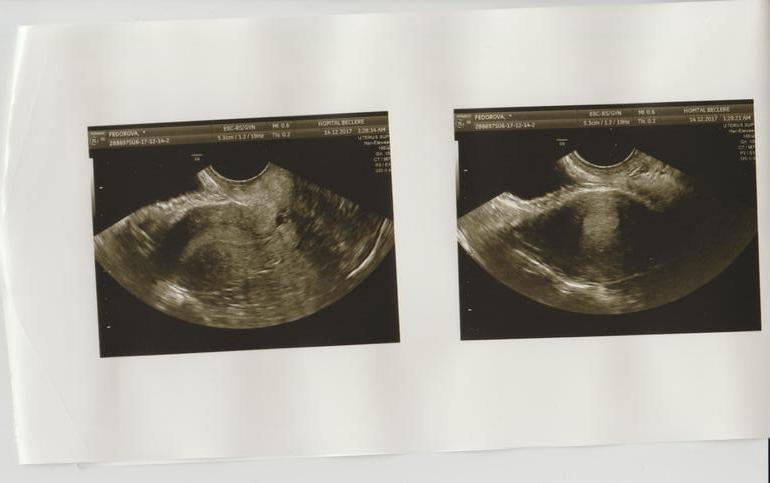

Правый, левый. И в углу видимо размеры, диаметр чего-то..н5онятно чего, наверное фолликула? На какой дц делалаи? Вижу вооде эндометри на втором фото... очень интересное конечно дело...у себя записи делают они?

никаких записей. по мнению глав врача- первый день цикла. у меня кровит, но очень скудно и светло-розовый цвет. я обратилась к врачу, так как это не типично для меня и в прошлом цикле приходилось останавливать кровотечение.

в общем мне вручили УЗИ и послали домой с выводами, что это начало месячных.

Нет расшифровки . На словах врач сказала начало цикла.

Но у меня есть основани не доверять ее выводам и спросить тут на форуме если кто нибудь что то в этом понимает